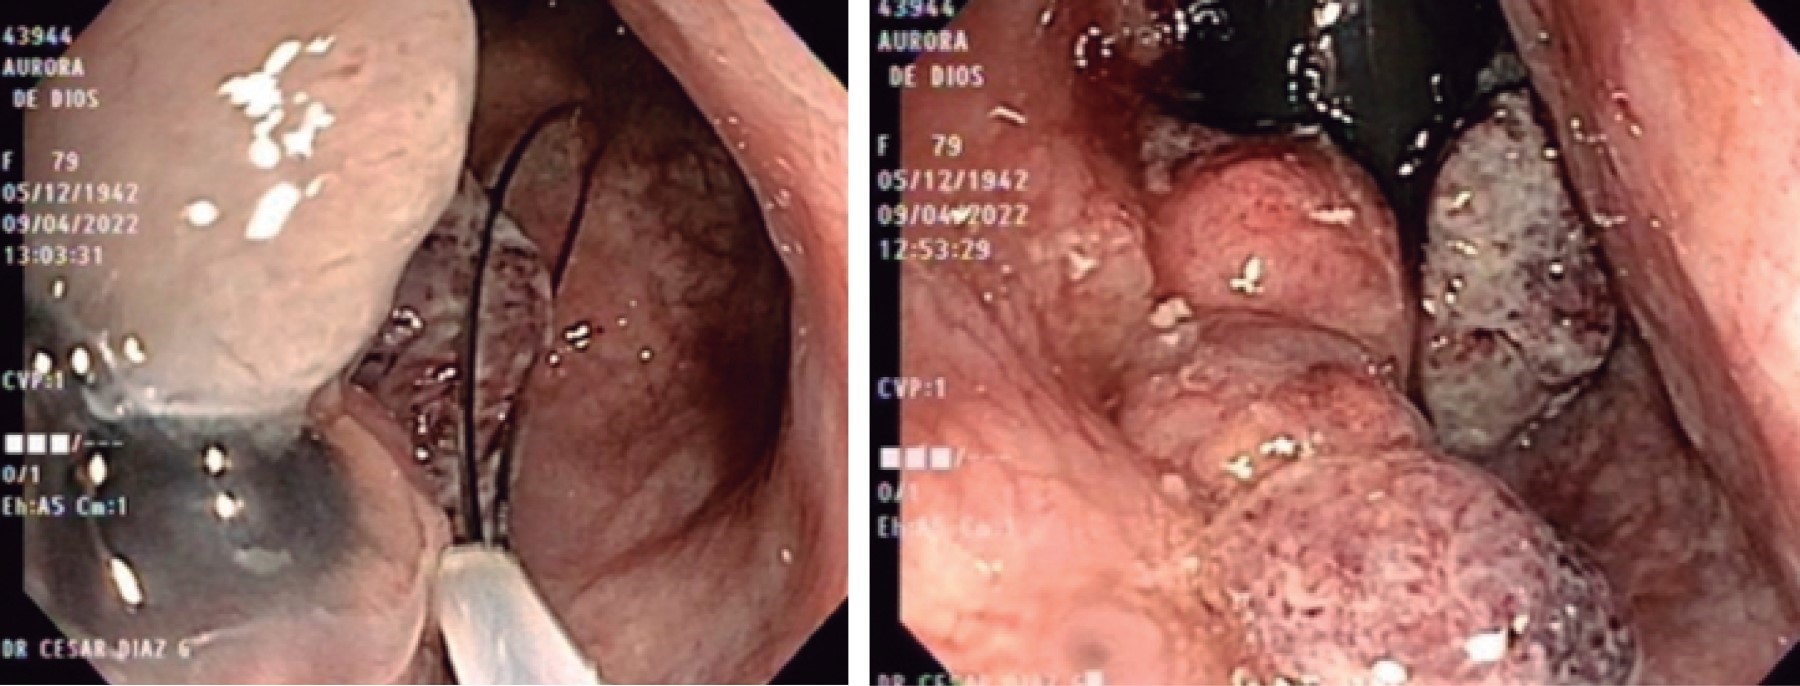

Femenino de 79 años, sin antecedentes de importancia, que acude a la consulta externa de medicina general por presentar sangrado transrectal y evacuaciones diarreicas de aproximadamente una semana de evolución, que es manejada como enfermedad hemorroidal y brindan tratamiento tópico durante dos meses; sin embargo, persiste con dicha sintomatología además de sensación de masa anal y dolor al mismo nivel, por lo que acude al servicio de coloproctología donde a la exploración física se encuentra región perianal normal, sin evidencia de lesiones; al tacto rectal se palpa induración de aproximadamente 5 × 5 centímetros en canal anal a nivel lateral izquierdo, por lo que se realiza colonoscopia donde se evidencia tumoración elevada en ámpula rectal de aspecto polipoide de aproximadamente 20 mm con mucosa hiperémica, edematosa y friable. Se toma biopsia con asa de polipectomía (Figura 1), con reporte histopatológico de neoplasia maligna indiferenciada y ulcerada de región anorrectal, se lleva a cabo estudio de inmunohistoquímica con resultado positivo a Melan A y HMB 95, diagnosticándose melanoma maligno ulcerado. Se realizan estudios de extensión con tomografía computarizada toracoabdominopélvica simple y contraste intravenoso, sin evidencia de enfermedad metastásica ni de adenopatías inguinales; reportándose engrosamiento de las paredes del recto de hasta 50 mm con morfología de tipo anular. La resonancia magnética reporta lesión en recto inferior/canal anal, sin cambios en grasa perirrectal, sin alteraciones en mucosa adyacente.

Se decide programar para resolución quirúrgica mediante resección abdominoperineal. Previo a procedimiento se realiza biopsia de ganglio inguinal derecho centinela transoperatorio con reporte negativo a neoplasia maligna y se procede a resección abdominoperineal. Se realiza abordaje por vía laparoscópica, realizando laparoscopia diagnóstica sin evidencia de actividad tumoral a distancia, se procede a disección de mesorrecto junto a disección de arteria y vena mesentérica inferior con energía avanzada y se realiza corte a nivel del pedículo vascular con engrapadora, se realiza colostomía en cabo proximal sin complicaciones. En fase perineal se seccionan músculos del esfínter, así como ligamentos y grasa perirrectal, completando disección de recto en porción perineal, sin colocación de drenajes, afrontando por planos. El estudio anatomopatológico de la pieza de resección rectosigmoidea (Figura 2) confirmó la presencia de melanoma nodular maligno, de mucosa ano-rectal, diámetro mayor de cinco centímetros, con infiltración hasta la submucosa y metástasis a dos de 10 ganglios linfáticos de mesorrecto; márgenes quirúrgicos libres de neoplasia. En la imagen de histopatología se aprecian células fusiformes con núcleos atípicos y con pigmento melánico en su interior (Figura 3). Se envía a oncología médica indicando que la paciente es candidata a inmunoterapia con pembrolizumab adyuvante; sin embargo, el tratamiento no es autorizado, por lo que únicamente se mantiene en vigilancia periódicamente. Actualmente, ocho meses posteriores a intervención quirúrgica, continúa seguimiento por coloproctología, con adecuada evolución sin demostrar alteraciones a nivel de colostomía y libre de enfermedad.